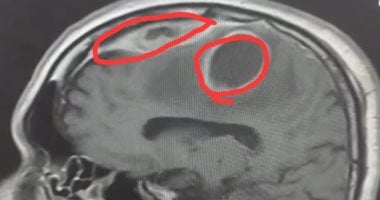

نجح فريق جراحة المخ والأعصاب بمستشفى دمياط العام، في إجراء عملية دقيقة لاستئصال خراج بالمخ لشاب، بعد معاناة استمرت لأكثر من عام ونصف مع آلام حادة وتشنجات مستمرة. في إنجاز طبي جديد يُضاف إلى سجل القطاع الصحي بمحافظة دمياط، وتحت رعاية الدكتور حسام الدين فوزي، محافظ دمياط، وبمتابعة الدكتور محمد عبد ال...